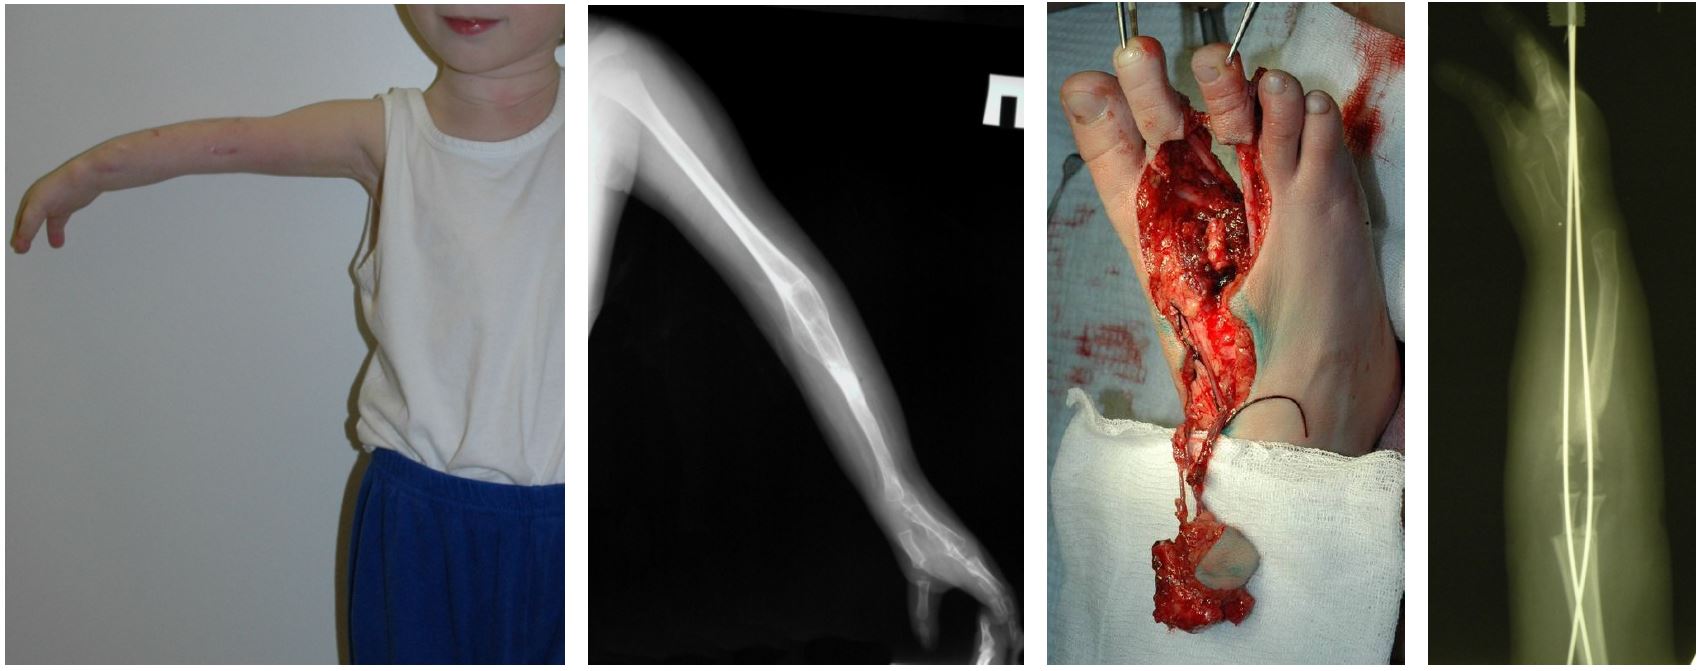

Техника проведения операции: по тыльной поверхности левой стопы произведен фигурный разрез в области 2-го и 3-го межпальцевых промежутков с формированием «буйкового лоскута». Выделены сосудистые пучки – большая подкожная вена с её ветвями ко 2-му и 3-му пальцам и тыльная артерия стопы, с ее продолжением в виде 2-го и 3-го тыльных плюсневых артерий. Разрез продолжили на подошвенную поверхность стопы. Произвели выделение 2–3-й подошвенных плюсневых артерий до уровня разветвления на собственные пальцевые артерии. Пересекли сухожилия сгибателей и разгибателей 2–3-го пальцев левой стопы. Выполнили остеотомию плюсневых костей и основных фаланг 2–3-го пальцев, после чего единым блоком заимствовали аутотрансплантат 2–3-го плюсне-фаланговых суставов на сосудистой ножке. При этом для питания 2–3-го пальцев (от уровня основных фаланг до ногтевых фаланг) сохранены подошвенные собственные пальцевые артерии, получающие кровоток из 1-й и 4-й подошвенных плюсневых артерий. В реципиентной зоне по передней поверхности правой верхней конечности в проекции синостоза произвели S-образный разрез. Лоскут окружающих мягких тканей мобилизован. Выделен дистальный отдел плечевой и участок лучевой артерии, а также латеральная подкожная вена. Для создания диастаза между лучевой и плечевой костями выполнили остеотомию с резекцией зоны их синостоза на протяжении 3 см. В образовавшийся диастаз внедрили аутотрансплантат блока 2–3-го ПФС и фиксировали по оси сегмента двумя спицами Киршнера. Далее наложили микрососудистые анастомозы между сосудами донорской и реципиентной области. Оценку адекватности кровотока производили благодаря включению в аутотрансплантат «буйкового лоскута». С целью восстановления опороспособности левой стопы одномоментно провели ее реконструкцию. Верхнюю и нижнюю конечности иммобилизировали гипсовыми лонгетами (рис. 1).

Рис. 1. Пациент А.: а – внешний вид верхней конечности до проведения микрохирургической аутотрансплантации блока 2–3-го ПФС в позицию правого локтевого сустава; б – рентгенограмма верхней конечности до проведения микрохирургической аутотрансплантации блока 2–3-го ПФС в позицию правого локтевого сустава; в – этап оперативного вмешательства – выделен аутотрансплантат блока 2–3-го ПФС; г – рентгенограмма верхней конечности после проведения микрохирургической аутотрансплантации блока 2–3-го ПФС в позицию правого локтевого сустава